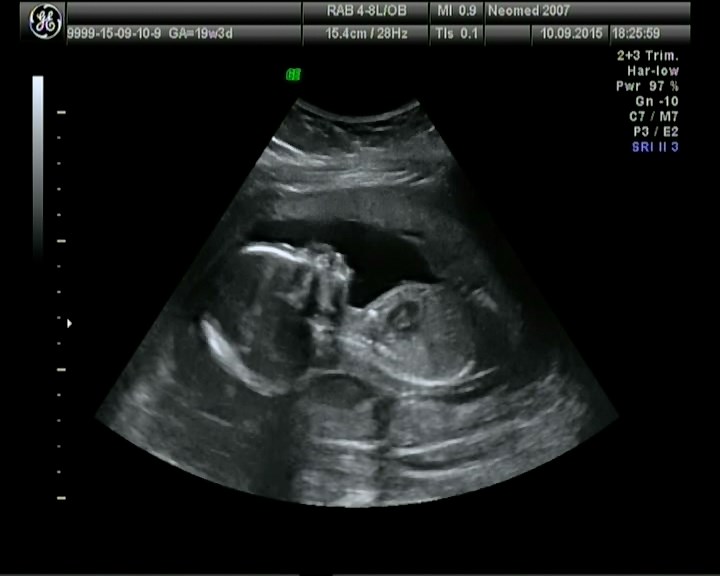

На второе скрининговое узи сходили вместе с мужем к очень хорошему узисту,с отличной аппаратурой.В Мед.Центр Мать и Дитя,мы были в вросторге и от клиники и от узиста,все четко,померял даже каждую почку,печень,мочевой,посмотрел камеры сердца,доплером посмотрел кровоток и даже записал нам диск на память.

Много фоточек вытянула из видео)

Тут явно видно кого мы ждем)))